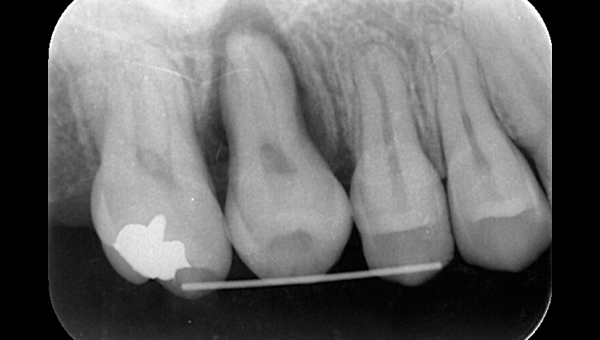

初診時のパノラマレントゲン

説明:

初診時のパノラマレントゲンです。右上の歯が虫歯によって大きく欠けているのがわかります。